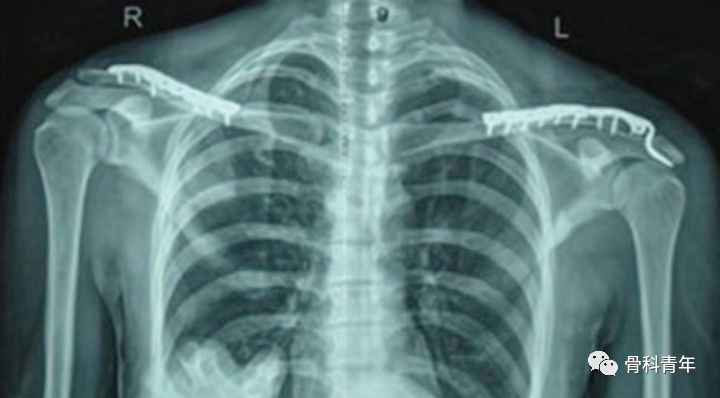

对此类型损伤,通常有几种手术方案,包括长钩钢板、锁骨钢板+钩钢板、锁骨钢板+螺钉固定锁骨至喙突等。但钩钢板长度总体长度较短,近端可能固定不牢靠,锁骨钢板+钩钢板会存在连接处的应力集中,容易再骨折。

左锁骨骨折合并同侧肩锁关节脱位,采用钩钢板+锁骨钢板固定。